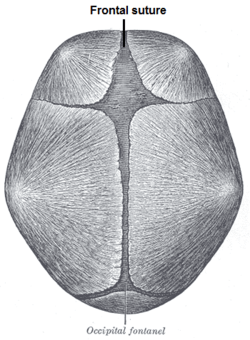

| Human baby skull seen from top. Cranial sutures are depicted. Frontal suture is highlighted in blue. |